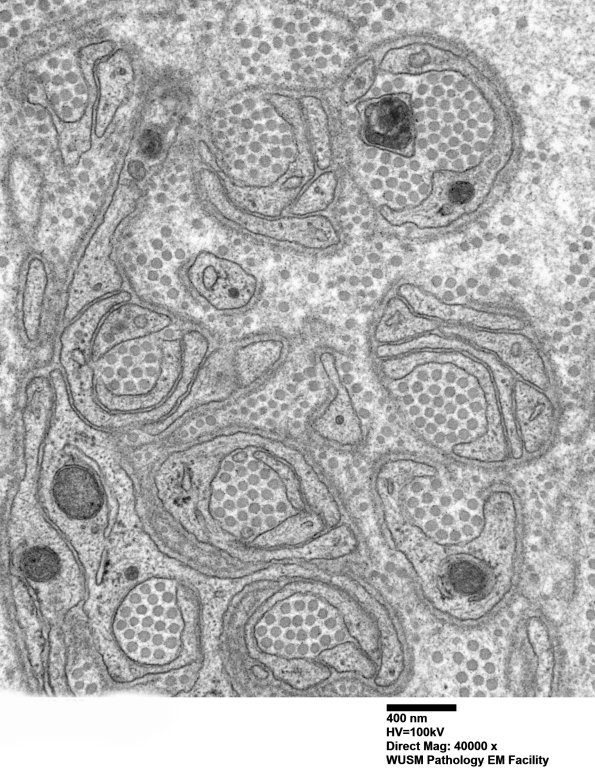

Small numbers of “collagen pockets”, characterized by Schwann cell processes surrounding groups of collagen fibers, are normal in nerve as a way of Schwann cells of unmyelinated axons maintaining a stable relationship within the endoneurium